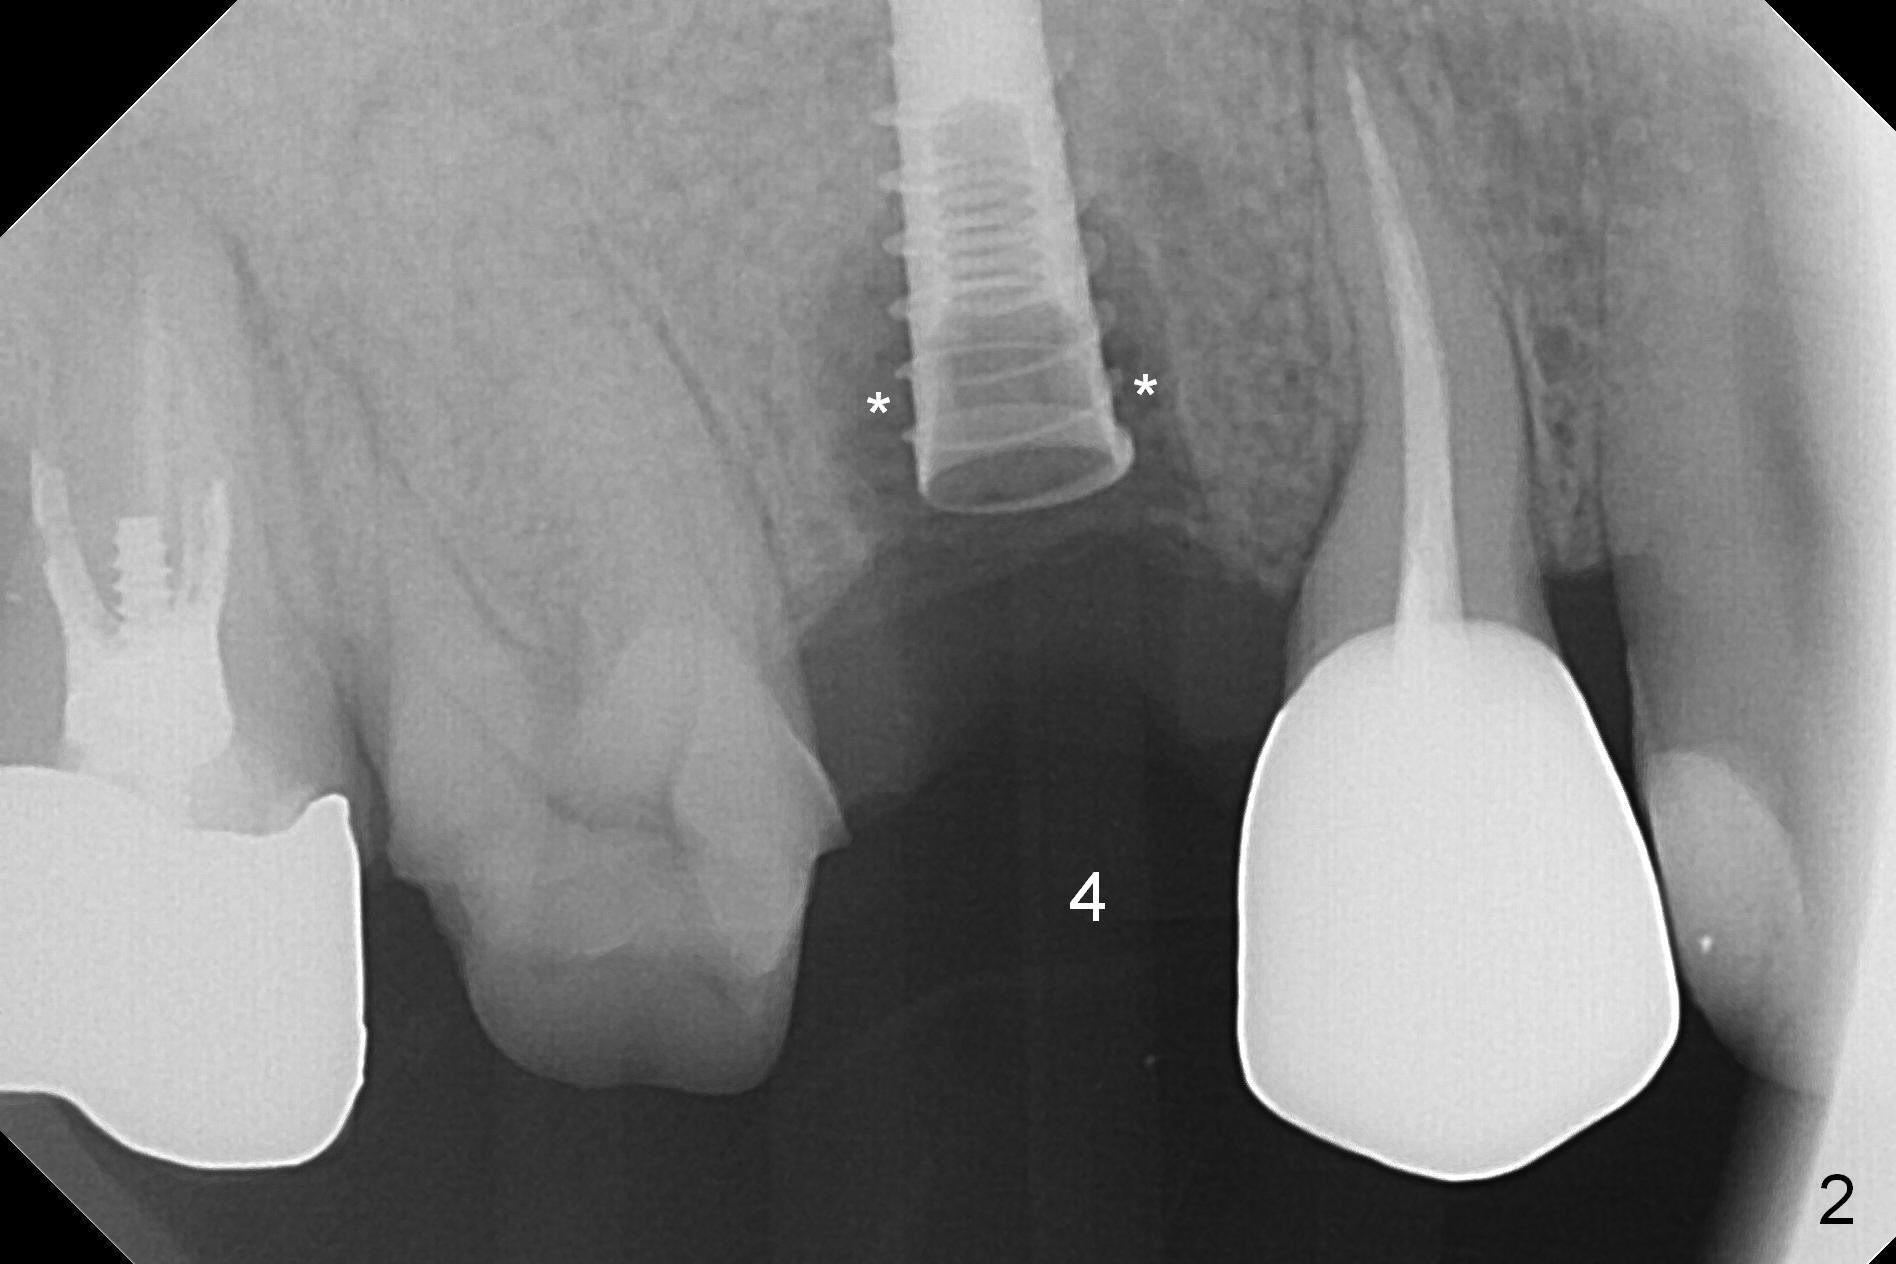

When the tooth #4 with vertical root fracture is extracted, the socket is large, approximately 6x10x10 mm (Fig.1 (mesiodistal x buccopalatal width x depth)). Osteotomy is established in the middle of the socket with 2 mm initial drill for 7 mm, 2.8 and 3.6 mm rounds drills (from DIO Sinus Master Kit) for < 7 mm, and 3.0 and 3.8 mm Magic Expanders. A 4x11 mm dummy implant is placed with insertion torque of 30 Ncm (Fig.2,3 (^: sinus floor)). There is a gap between the socket wall and the implant (*). To reduce the gap and periimplantitis, a 5x11 mm IBS implant is placed with insertion torque > 50 Ncm after further osteotomy using Magic Drills (Fig.4,5). Following placement of 5.5x4(4) mm abutment (A) and bone graft (data not shown), a splinted provisional is fabricated at #3 and 4. The provisional is stable 3 months postop (Fig.6,7). The peri-implant gaps (Fig.4,5) seem to disappear (Fig.6) with the help of bone graft. Bone graft appears to remain between the implant fins (Fig.7 arrows). Impression is taken 4.5 months postop (Fig.8,9). The abutment dislodges 4 months post cementation. After retightening, there is clearance for shim after use of 2 layers of thick articulating paper. Is the abutment screw too short? Or Titanium V is too hard for welding? The abutment/crown dislodges again 1 year 3 month post cementation; it appears that the fact that the implant is placed deep contributes to abutment screw loosening (Fig.10,11). An abutment screw will be buried inside the implant well 10 days post initial retightening.